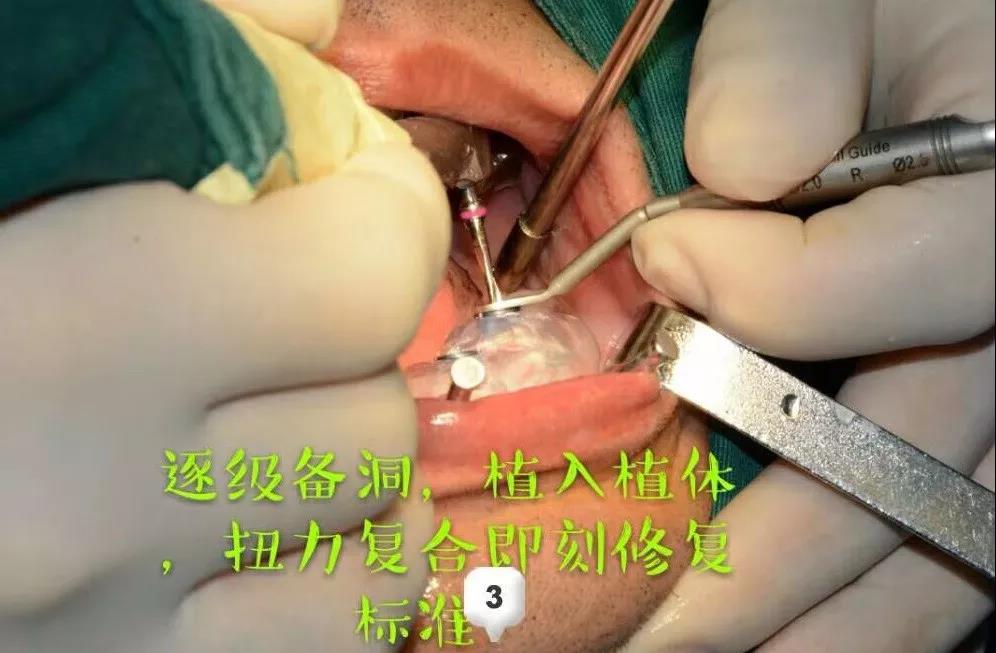

第一次耗时两个多小时:先进行了术前的测量评估,指定手术方案;术中采用数字化种牙导板,精准定位;逐级备洞,植入植体,扭力复合完成植入上半口。